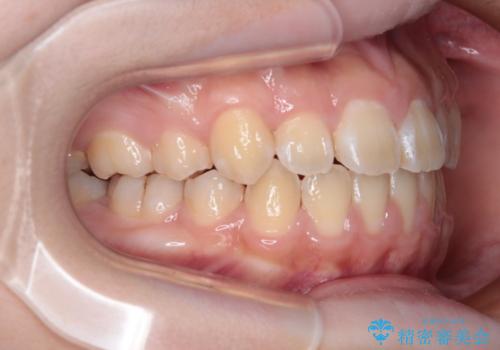

舌の突出癖により上下前歯は接触できず、更には前方に押し出されて出っ歯になっている状態でした。

上下左右の第一小臼歯4本を抜歯し、ワイヤー装置での抜歯矯正を行っていくのですが、原因である舌の突出癖を改善しないことには治療がうまく進められないため、舌のトレーニングを徹底するよう指導していくこととしました。